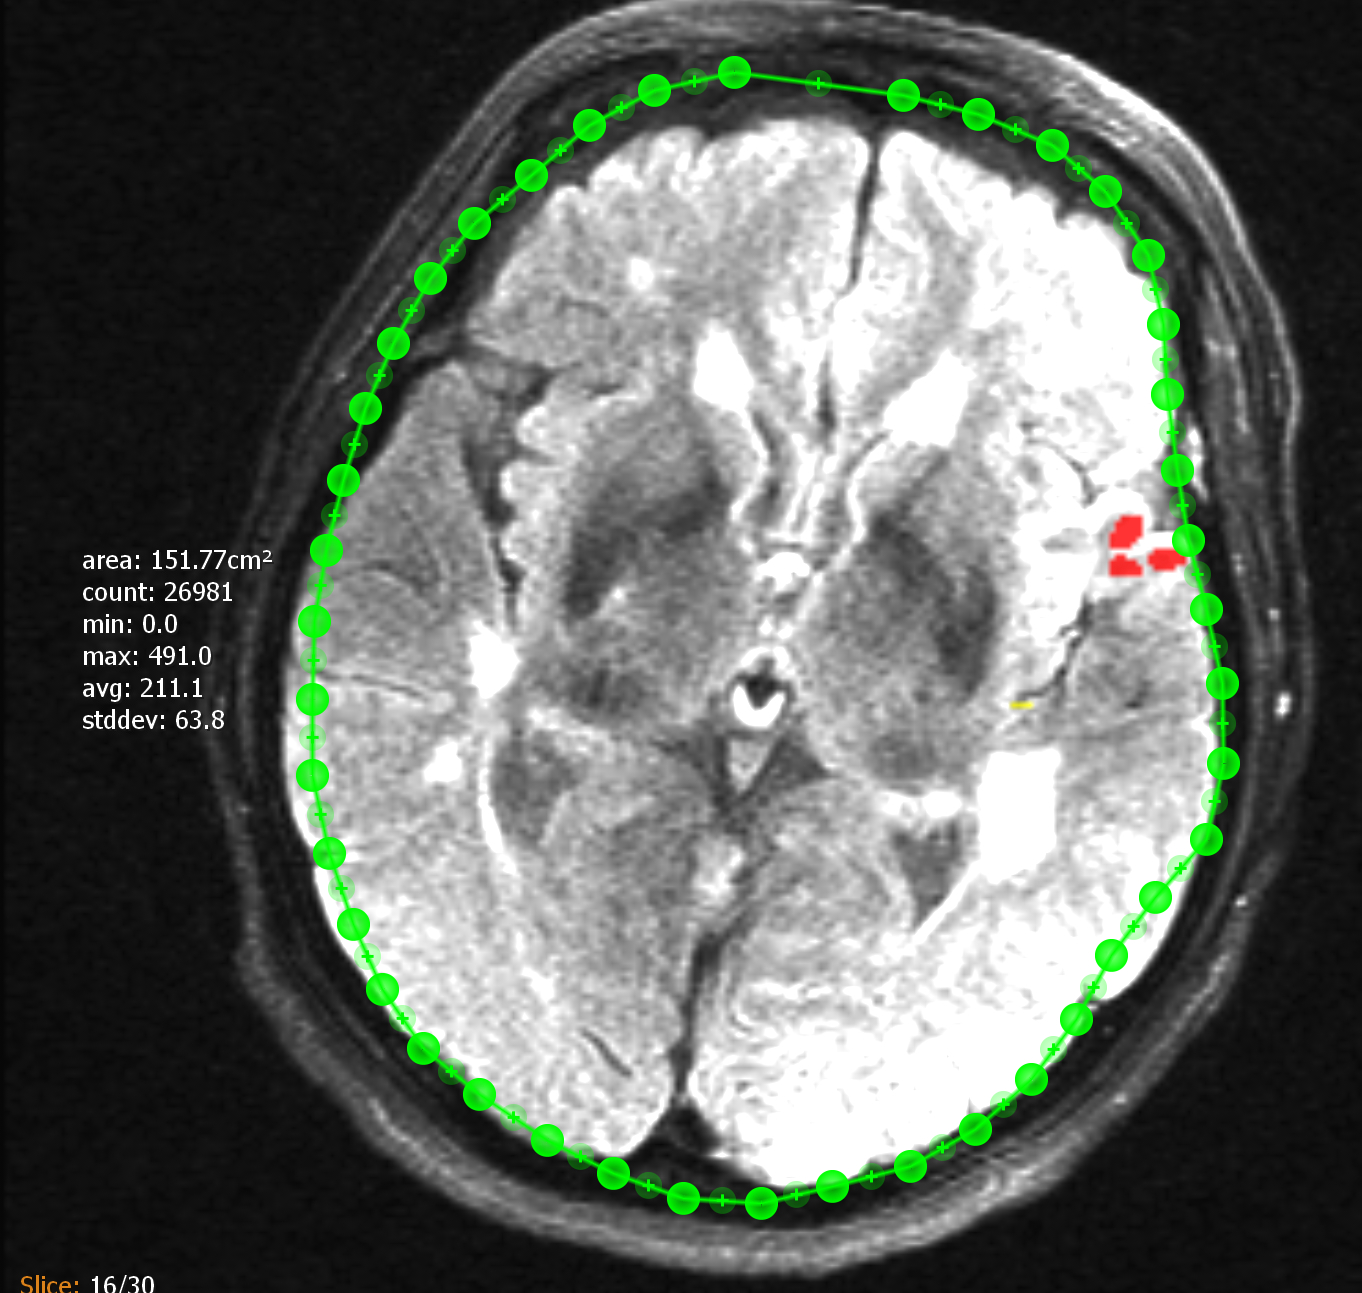

11.1.6. Segmentierung

Über das "Segmentierung"-Werkzeug können Sie eine manuelle Segmentierung in ein Schichtbild einfügen. Nach dem aktivieren umkreisen Sie das zu segmentierende Objekt mit dem Finger. Die Annotation lässt sich im Anschluss anpassen. Die Punkte der Segmentierung lassen sich einfach verschieben oder mit Doppelt-Tap löschen. Neue Punkte können durch '+' hinzugefügt werden. An der Seite der Segmentierung befindet sich ein zusätzlicher Informationstext, welcher folgende berechneten Werte über die in der Segmentierung liegenden Pixel enthält:

-

area: Segmentierte Fläche (optional, wenn Bild Spacing korrekt).

-

count: Anzahl der Pixel innerhalb der Segmentierung.

-

min: Kleinster in der Segmentierung enthaltene Grauwert.

-

max: Größter in der Segmentierung enthaltene Grauwert.

-

avg: Durchschnittlicher Grauwert über alle in der Segmentierung enthaltenen Grauwert.

-

stddev: Standardabweichung / gemittelter Abstand der Streuung aller Grauwerte zum durchschnittlichen Grauwert der in der Segmentierung enthaltenen Pixel.